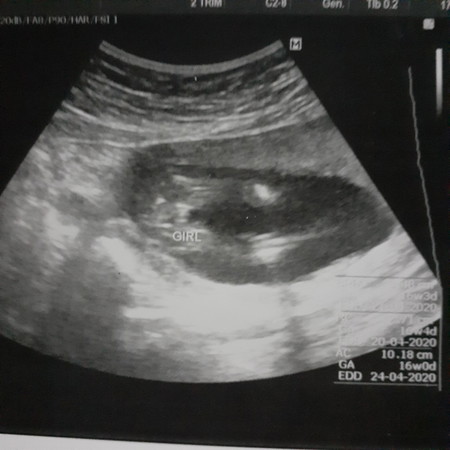

หญิงค่ะ ไม่มีจู๋และเห็นกลีบค่อนข้างชัด แถมคุณหมอระบุแล้วด้วยว่า girl เพศ เป็นสิ่งที่เด็กเกิดและโตขึ้นมาเลือกเองค่ะ เพียงแค่เขาจะเกิดมาในร่างกายแบบไหนก็เท่านั้นเอง ต่อให้ใช้เงินจำนวนมาก พึ่งวิธีวิทยาศาสตร์ ให้ร่างกายออกมาเป็นชาย แต่ท้ายที่สุดแล้ว ใจจริงของเขาจะเป็นชายหรือหญิงนั้น ก็เป็นสิ่งที่เขาโตมาเลือกเองอยู่ดีค่ะแม่

อ่านเพิ่มเติม16 วีคเห็นชัดมากค่ะ ตัวเล็กบ้านนี้ 18 วีคไม่เห็นไรเลย น่าจะผู้ ญ เหมือนบ้านนี้ค่ะ

บ้านนี้ก็เพศหญิงค่ะ เป็นกลีบๆน่าจะเพศหญิงนะค่ะ ไม่มีจู๋โผล่

หมอระบุชัดเจนนะคะ Girl คือผู้หญิงค่ะ

เขาเขียนว่าGIRL ผู้หญิงคะ

เหมือนเป็นกลีบนะคะคุณแม่

คะหมอบอกว่า3กลีบชัดเจนคะ